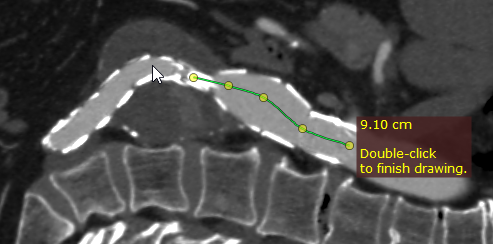

点击鼠标左键放置起始节点,重复此操作沿要测量的结构放置其余节点。

绘制开放多边形

如有需要,绘制完成后可以修改形状。双击图像完成绘制。